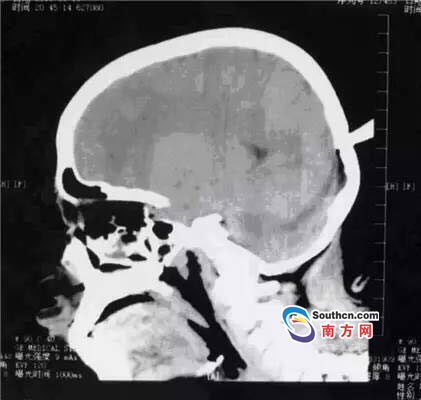

接到小玲受傷的消息,東莞市第三人民醫(yī)院急診科立即啟動(dòng)了急癥危重患者搶救流程。急癥頭部CT顯示,飛鏢已穿透小玲的顱骨,并突破硬腦膜,情況非常兇險(xiǎn),小玲命懸一線。